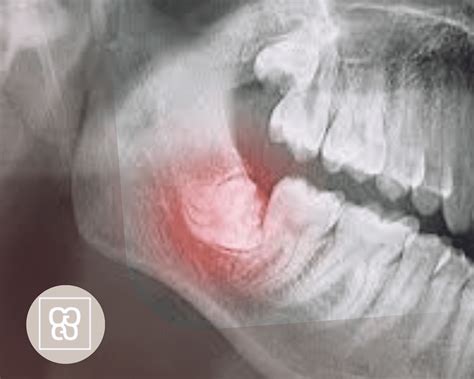

En ocasiones estos molares se desarrollan bien y brotan sin problemas. Pero hay casos en los que no tienen suficiente espacio. Esto causa que queden retenidas o salgan solo de forma parcial. En este último caso puede ocurrir que crezca en ángulo hacia el segundo molar o hacia atrás; o que esté derecha, pero atrapada en el maxilar.

La formación de quistes es otro de los problemas que pueden afectar. El dolor y las infecciones también son posibles problemas que pueden aparecer debido a las muelas impactadas.